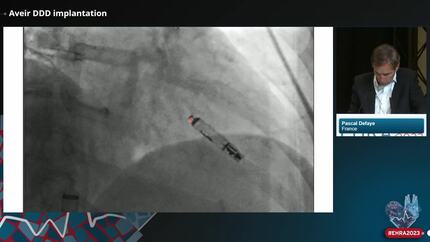

EHRA 2023

18 April 2023